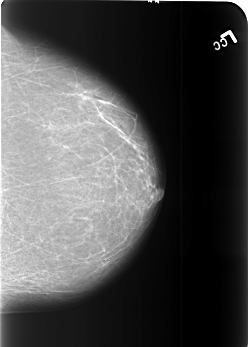

B_3451_1.LEFT_CC

LEFT_CC LINES 5544 PIXELS_PER_LINE 3968 BITS_PER_PIXEL 12 RESOLUTION 50 NON_OVERLAY